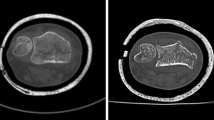

Following the consensus reading, 28 patients with fractures of the distal upper, i.e. hand and wrist, and 18 patients with fractures of the distal lower extremity, i.e. foot and ankle, were scanned (Table 1). In total, 92 fractures were present on CT with 46 each of the upper and lower distal extremities, respectively. Single fractures were present in 18 patients (14 upper/4 lower distal extremities), 2 simultaneous fractures were present in 16 patients (8 upper/8 lower distal extremities), 3 simultaneous fractures in 8 patients (4 upper/4 lower distal extremities), 4 simultaneous fractures in 2 patients (1 upper/1 lower distal extremities), and 5 simultaneous fractures in 2 patients (0 upper/2 lower distal extremities). Eighty-six of these 92 fractures (93%) were visible on 3D tomography (43 of 46 fractures of each upper and lower distal extremities; Figs. 1 and 2). Six fractures (7%) in three patients were missed on 3D tomographic images (Table 1): avulsion fractures of the triquetrum (n = 1), 2nd metacarpal (n = 1; Fig. 3), lateral cuneiform (n = 1), 2nd metatarsal (n = 1), 3rd metatarsal (n = 1; Fig. 4), and one nondisplaced fracture of the capitate (n = 1; Fig. 5). Out of these, two fractures in one patient were not visible due to higher noise on 3D tomography (Fig. 3), and four fractures in two patients were not visible due to severe artifacts in 3D tomography (motion artifacts (Fig. 4), and an increased noise related to cast fixation (Fig. 5)). No fracture was diagnosed false positive on 3D tomographic images.

Right foot of an 18-year-old male with multiple tarso-metatarsal fractures. The displaced fractures of the navicular and cuboid bone (arrows) were seen on 3D tomography (a) and CT images (b). Two avulsion fractures at the second and third metatarsal bone were only diagnosed on CT (arrowheads) but missed on 3D tomography due to motion artifacts (black arrowheads)

Left hand in cast fixation of a 76-year-old female imaged with twin robotic X-ray (a) and CT (b) shows an impacted and displaced radius fracture (asterisk). The additional nondisplaced fracture of the capitate was diagnosed on CT (arrowhead in b), but not diagnosed by both readers on 3D tomography (black arrowhead)